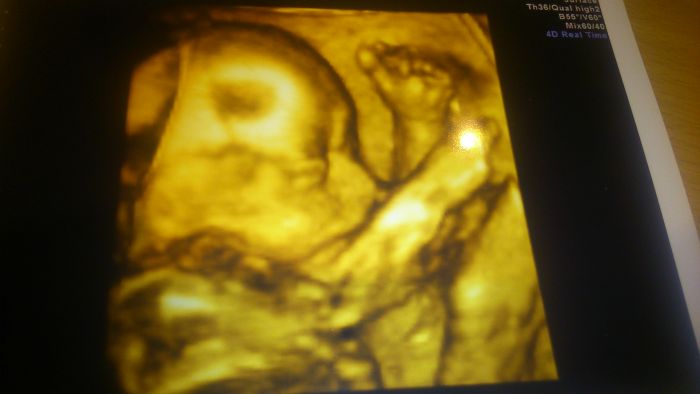

Napadolo mě, že je to asi můj poslední velký UTZ, takže máme naši první 3D fotečku;-)

Hanul .... nadherne zpravy a krasna fotecka. Je super, ze je vse v poradku. Gratulace k holcicce

Hanulo ,super zprávy!! a moc hezká fotečka!!

Hanula krásná fotecka a gratuluji k výsledkům a pohlaví